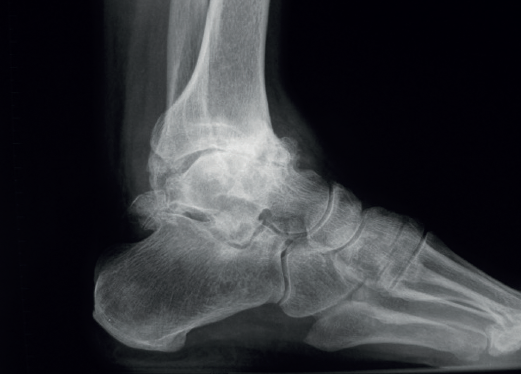

Debemos observar si, en las proyecciones laterales, existe una traslación anterior del astrágalo que muchas veces ocurre en estos fenómenos degenerativos crónicos asociados a inestabilidades (Figura 2).

Figura 2. Traslación anterior del astrágalo, característica de las artropatías tibioastragalinas secundarias a inestabilidades crónicas.